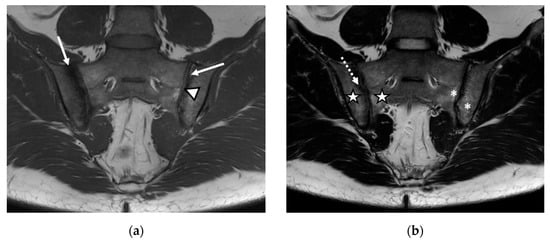

Figure 1.

The magnetic resonance imaging (MRI) examination of the sacroiliac joints revealed narrowing of the sacroiliac joint spaces with bilateral marginal bone erosions (continuous arrow), bilateral subchondral sclerosis (arrowhead), and increased fat metaplasia (star), with minimal diffuse adjacent bone marrow edema (dotted arrow): (a) T1-weighted sequence; (b) T2-weighted sequence; (c) short tau inversion recovery (STIR) sequence.